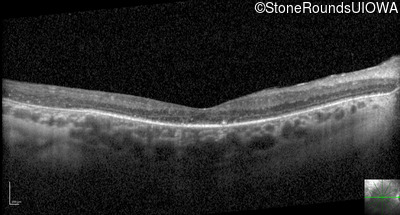

Optical Coherence Tomography - Left - 20/100

Exemplar / OCT Stack

OCT Stack